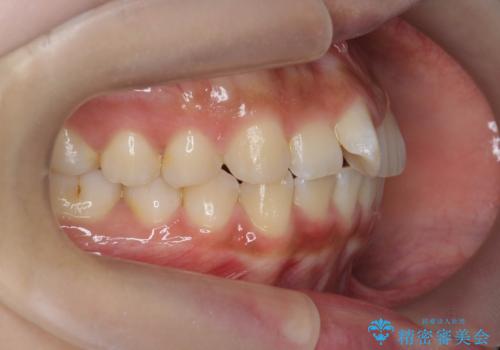

- 前歯の目立つねじれを矯正治療で治したい、と来院されました。

マウスピース矯正を始める前に、ねじれを取るのが短期間で済む部分ワイヤー小矯正を行うことで、全体的な治療期間を短くする治療計画を実行していきます。

前歯のねじれはマウスピース矯正の苦手な動きになり、治療期間が長くなる原因になりやすいです。